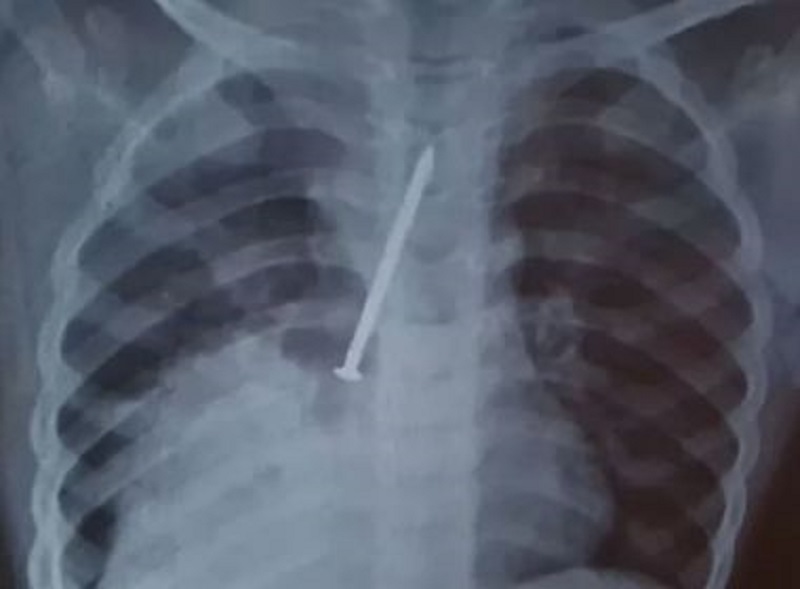

Foto: Reprodução l Redes Sociais